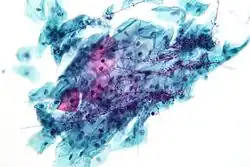

Candida

Candida species cause infections in individuals with deficient immune systems. Candida species tend to be the culprit of most fungal infections and can cause both systemic and superficial infection.[6] Th1-type cell-mediated immunity (CMI) is required for clearance of a fungal infection. Candida albicans is a kind of diploid yeast that commonly occurs among the human gut microflora. C. albicans is an opportunistic pathogen in humans. Abnormal over-growth of this fungus can occur, particularly in immunocompromised individuals.[7] C. albicans has a parasexual cycle that appears to be stimulated by environmental stress.[8]

Other species of Candida may be pathogenic as well, including Candida stellatoidea, C. tropicalis, C. pseudotropicalis, C. krusei, C. parapsilosis, and C. guilliermondii.[9]